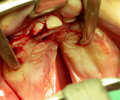

Las técnicas quirúrgicas que aplicamos a los niños fisurados son las más avanzadas y aceptadas internacionalmente, con resultados de alta calidad. En su primer mes de vida y sólamente sí lo precisa, le colocamos en su boquita ORTOPEDIA PREQUIRÚRGICA. A los 3 meses operamos el labio, la nariz y la encía. A los 12 meses se interviene la fisura palatina. Al año el niño está definitivamente corregido.

El tratamiento de los niños con fisura facial debe ser integral y realizado por un equipo multidisciplinar, para así obtener los mejores resultados funcionales y estéticos.